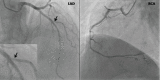

Herein, we report the case of a 56-year-old male patient with acute myeloid leukemia (AML) in remission who had asymptomatic myocardial ischemia on myocardial perfusion imaging and transthoracic echocardiography. Angiography did not reveal any significant coronary artery disease. Although the etiology is not entirely clear, this case suggested that myocardial perfusion imaging should be considered in patients with AML who received idarubicin to screen for possible myocardial dysfunction.